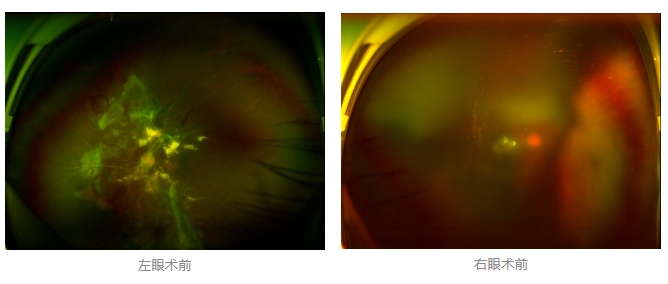

經(jīng)廈門(mén)眼科中心眼底病專(zhuān)科行政主任王曉波檢查后,確診其雙眼糖尿病視網(wǎng)膜病變VI期,伴發(fā)雙眼視網(wǎng)膜脫離和黃斑水腫,且右眼視網(wǎng)膜上增殖膜叢生,若再不盡快進(jìn)行治療,恐有失明風(fēng)險(xiǎn)。

面對(duì)陳先生的復(fù)雜病情,王曉波主任采用玻璃體切割術(shù)聯(lián)合膜切除術(shù)等方式,精細(xì)剝離牽拉視網(wǎng)膜的增殖膜,復(fù)位脫離的視網(wǎng)膜,同時(shí)進(jìn)行玻璃體腔注藥促進(jìn)黃斑水腫吸收。

經(jīng)過(guò)規(guī)范化治療,術(shù)后2個(gè)月復(fù)查時(shí)陳先生的視力已有明顯改善,矯正視力從眼前指數(shù)提升至0.3,成功擺脫“失明危機(jī)”。但王曉波主任強(qiáng)調(diào):“這只是階段性勝利,后續(xù)治療不能松懈。”